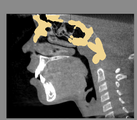

For assessment of overall facial changes, cranial base segmented models are only used to mask anatomic structures that change with growth and treatment. The registration procedures actually compare voxel by voxel of gray-level CBCT images, containing only the cranial base, to calculate rotation and translation parameters between the 2 images. Cranial base registration yields information of facial displacements relative to the cranial base. For subjects in whom cranial base growth is complete, registration is done using the gray level CBCT datasets of the whole cranial base ( Nongrowing registration module). The larger the number of voxels used for the registration, the more robust the registration is. For this reason, for adult patients the whole cranial base “mask CBCT” is used for registration. For growing patients ( Growing registration module), the registration includes two steps in the same module: in the first, an initial head alignment is done using the whole cranial base, and then a finer registration is performed at the stable structure on the anterior cranial base. For assessment of localized facial changes, such as mandibular or maxillary growth or bone remodeling of the mandibular condyle or tooth movement, specific anatomic regions can be used to create localized masks and aid regional superimpositions. The challenge in regional superimpositions is to determine which structures offer stable reference for registration.

- Mask creation: segmentation files are used to : 1: generate CBCT files that can be used to mask anatomic regions that changed with growth and treatment ; or 2: generate a CBCT file that contains only the anatomic region of interest for regional superimpositions.